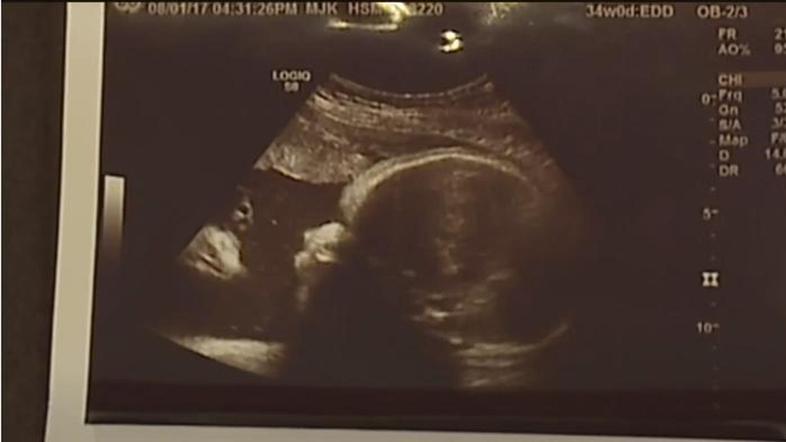

Starša šokirana, ko sta dobila slike dojenčice po ultrazvoku

To je jasen znak, trdita starša.

Ko sta Alicia Zeek in Zac Smith videla fotografije z ultrazvoka svoje še nerojene hčerke, sta vedela, da je to Božji znak. Poleg obraza dojenčice je po njihovem mnenju še en obraz, starša pa trdita, da njunega otroka gleda Jezus. Svojo zgodbo in tudi fotografije ultrazvoka sta želela deliti z javnostjo.

"Ko so nama dali fotografijo, sem takoj vedela, da gre za Jezusa. Tudi videti je tako," pravi Alicia iz Chambersburga v ameriški zvezni državi Pennsylvaniji. Z njo se strinja tudi oče Zac.

Par trdi, da nista pretirano verna in dodajata, da jima je fotografija dala upanje, saj sta se prva dva njuna otroka rodila s prirojenimi napakami. Hči ima dva palca na eni roki, sin pa je imel razcepljeno ustnico in nebo. Fotografija ultrazvoka je dala paru upanje, da se bo njuna hči rodila brez kakršnih koli prirojenih napak in da bo zdrava. Tako se je tudi zgodilo, ko se je Briella rodila.